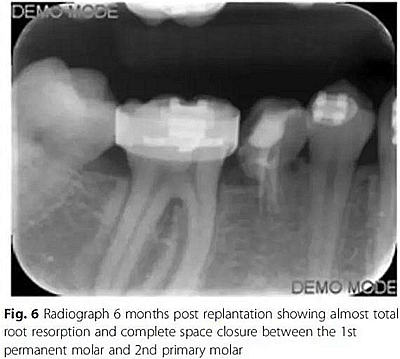

10周后,根據(jù)臨床和影像,形成乳磨牙牙槽粘連,移除牙弓夾板。下一步,在右下第一磨牙上粘接帶環(huán),在第二乳磨牙和下頜第一前磨牙上粘接托槽,在恒磨牙和乳磨牙之間安裝T型曲前移第一恒磨牙。T型曲共激活9次。

第6個月,臨床和影像檢查顯示乳牙幾近完全的替代性牙根吸收和間隙的完全關(guān)閉。最終,將乳磨牙拔除并開始進行完整的正畸治療。在接下來一年,用0.017’’*0.025’’末端回彎的不銹鋼弓絲和彈性牽引剩余間隙關(guān)閉,并以II類牽引作為支持。